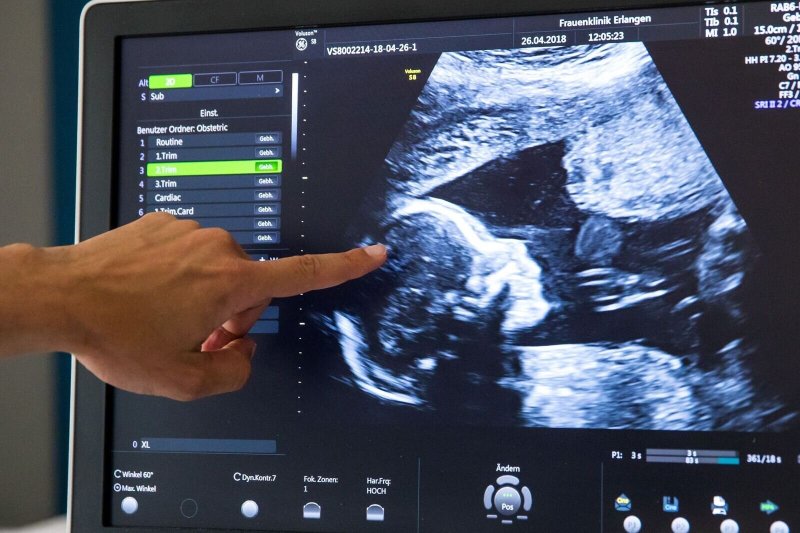

Seit einigen Jahren streiten Forscher darüber, wann unser Körper von Viren, Bakterien und anderen Mikroorganismen besiedelt wird. Während lange Zeit galt, dass dies erst im Verlauf der Geburt erfolgt, berichteten jüngere Studien, dass schon Fruchtwasser- und Plazentaproben solche Mikroorganismen enthielten. Das würde nahelegen, dass bereits Föten ein sogenanntes Mikrobiom haben. Ein internationales Team widerspricht dem nun deutlich: Aufgrund einer multidisziplinären Analyse, die im Fachblatt «Nature» veröffentlicht wurde, stellte es fest, dass der Mutterleib gewöhnlich doch steril ist.

Lange Zeit galt, dass das ungeborene Kind, sowie die Gebärmutter, in der es heranwächst, einschließlich der Plazenta (Mutterkuchen) und des Fruchtwassers bei einer gesunden Schwangerschaft steril sind. Seit 2010 berichteten jedoch mehrere Forschungsteams, Bakterien in Proben der Plazenta und des Fruchtwassers gefunden zu haben, und schlossen daraus auf das Vorhandensein eines fötalen Mikrobioms, was bedeuten würde, dass die gängige Vorstellung über die Entwicklung des Immunsystems beim Ungeborenen völlig neu bewertet werden müsste.

Die Autoren hoffen nun, dass ihr Konsens eine Orientierungshilfe für die künftige Forschung darstellt. «Er schafft eine solide wissenschaftliche Grundlage, um die Forschungsanstrengungen dort zu konzentrieren, wo sie am effektivsten sind», so Walter. Das Wissen, dass sich der Fötus in einer sterilen Umgebung befinde, bestätige, dass die Besiedlung mit Bakterien während der Geburt und in der frühen postnatalen Phase stattfinde – dies wurde auch von jüngsten Studien noch einmal belegt, denen zufolge Babys die ersten Mikroben während des Geburtsvorgangs und weitere durch die Muttermilch erhalten.